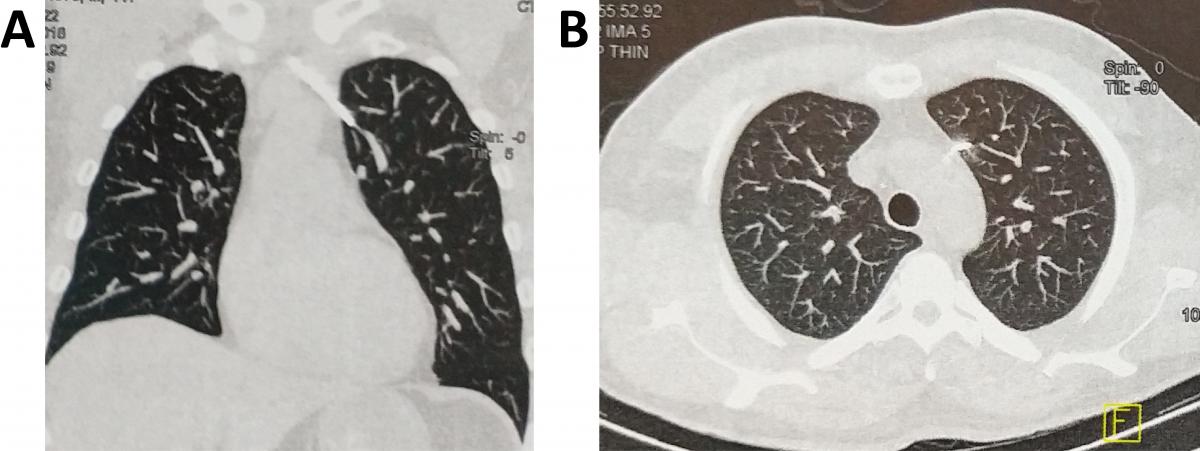

Figure 2. A) Chest CT (coronal plane) showing the K-wire perforating the left upper lobe. B) Chest CT (axial plane) showing the K-wire perforating the left upper lobe.

A chest computed tomography (CT) showed that the K-wire migrated through the anterior mediastinum into the left upper lobe (Figures 2A and 2B). In addition, a chest CT showed that the K-wire was encroaching on the left brachiocephalic vein, posing a risk to extraction of the foreign body (Figure 3A), and that it was anterior to the aortic arch (Figure 3B).